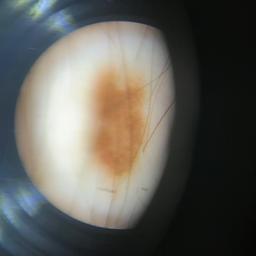

ISIC_8121870

acquisition_day 208

age_approx 70

anatom_site_1 Trunk

anatom_site_2 Posterior trunk

anatom_site_general posterior torso

concomitant_biopsy False

diagnosis_1 Benign

diagnosis_confirm_type single image expert consensus

family_hx_mm True

fitzpatrick_skin_type I

image_manipulation instrument only

image_type dermoscopic

lesion_id IL_5068664

patient_id IP_8705383

personal_hx_mm True

sex male